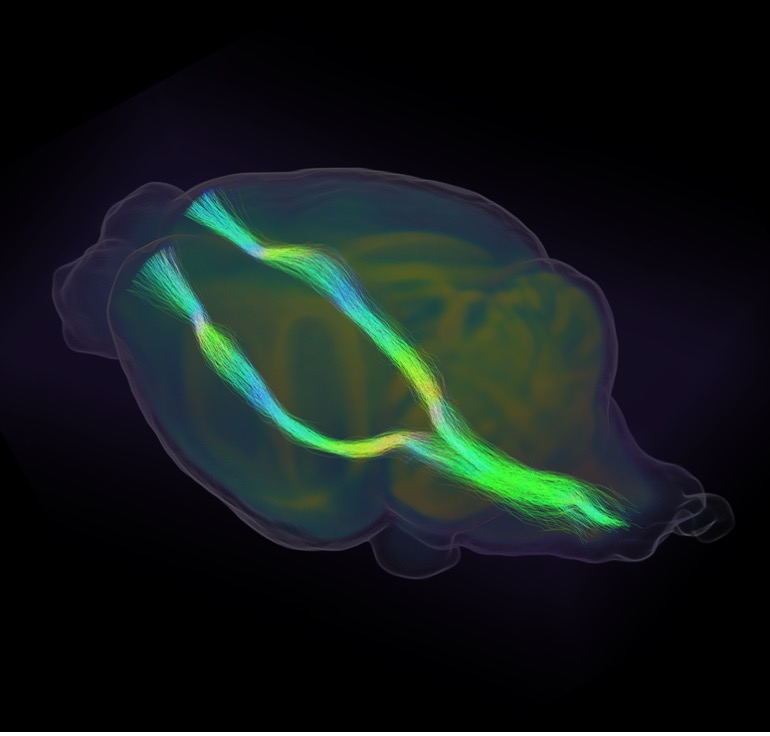

| Brain Imaging of Mouse Model with the Same PPID Gene Variant as the Family. Bird’s eye view of a mouse brain with the corticospinal tracts highlighted. The tracts are white matter bundles that connect the spinal cord (not shown) to the motor cortex and have developed abnormally due to the PPID variant. |

Chaperones are proteins that shuttle other proteins to the correct part of a cell so they can complete their function. We suspect the damaged PPID gene changes the movement and function of various proteins during brain development, triggering neural changes that cause persistent stuttering.

To test this, we generated a mouse model with the same gene defect, and the mice developed structural changes in similar brain regions to those of the family members with stuttering. This includes abnormalities of the corticospinal tracts which support speech and language development.